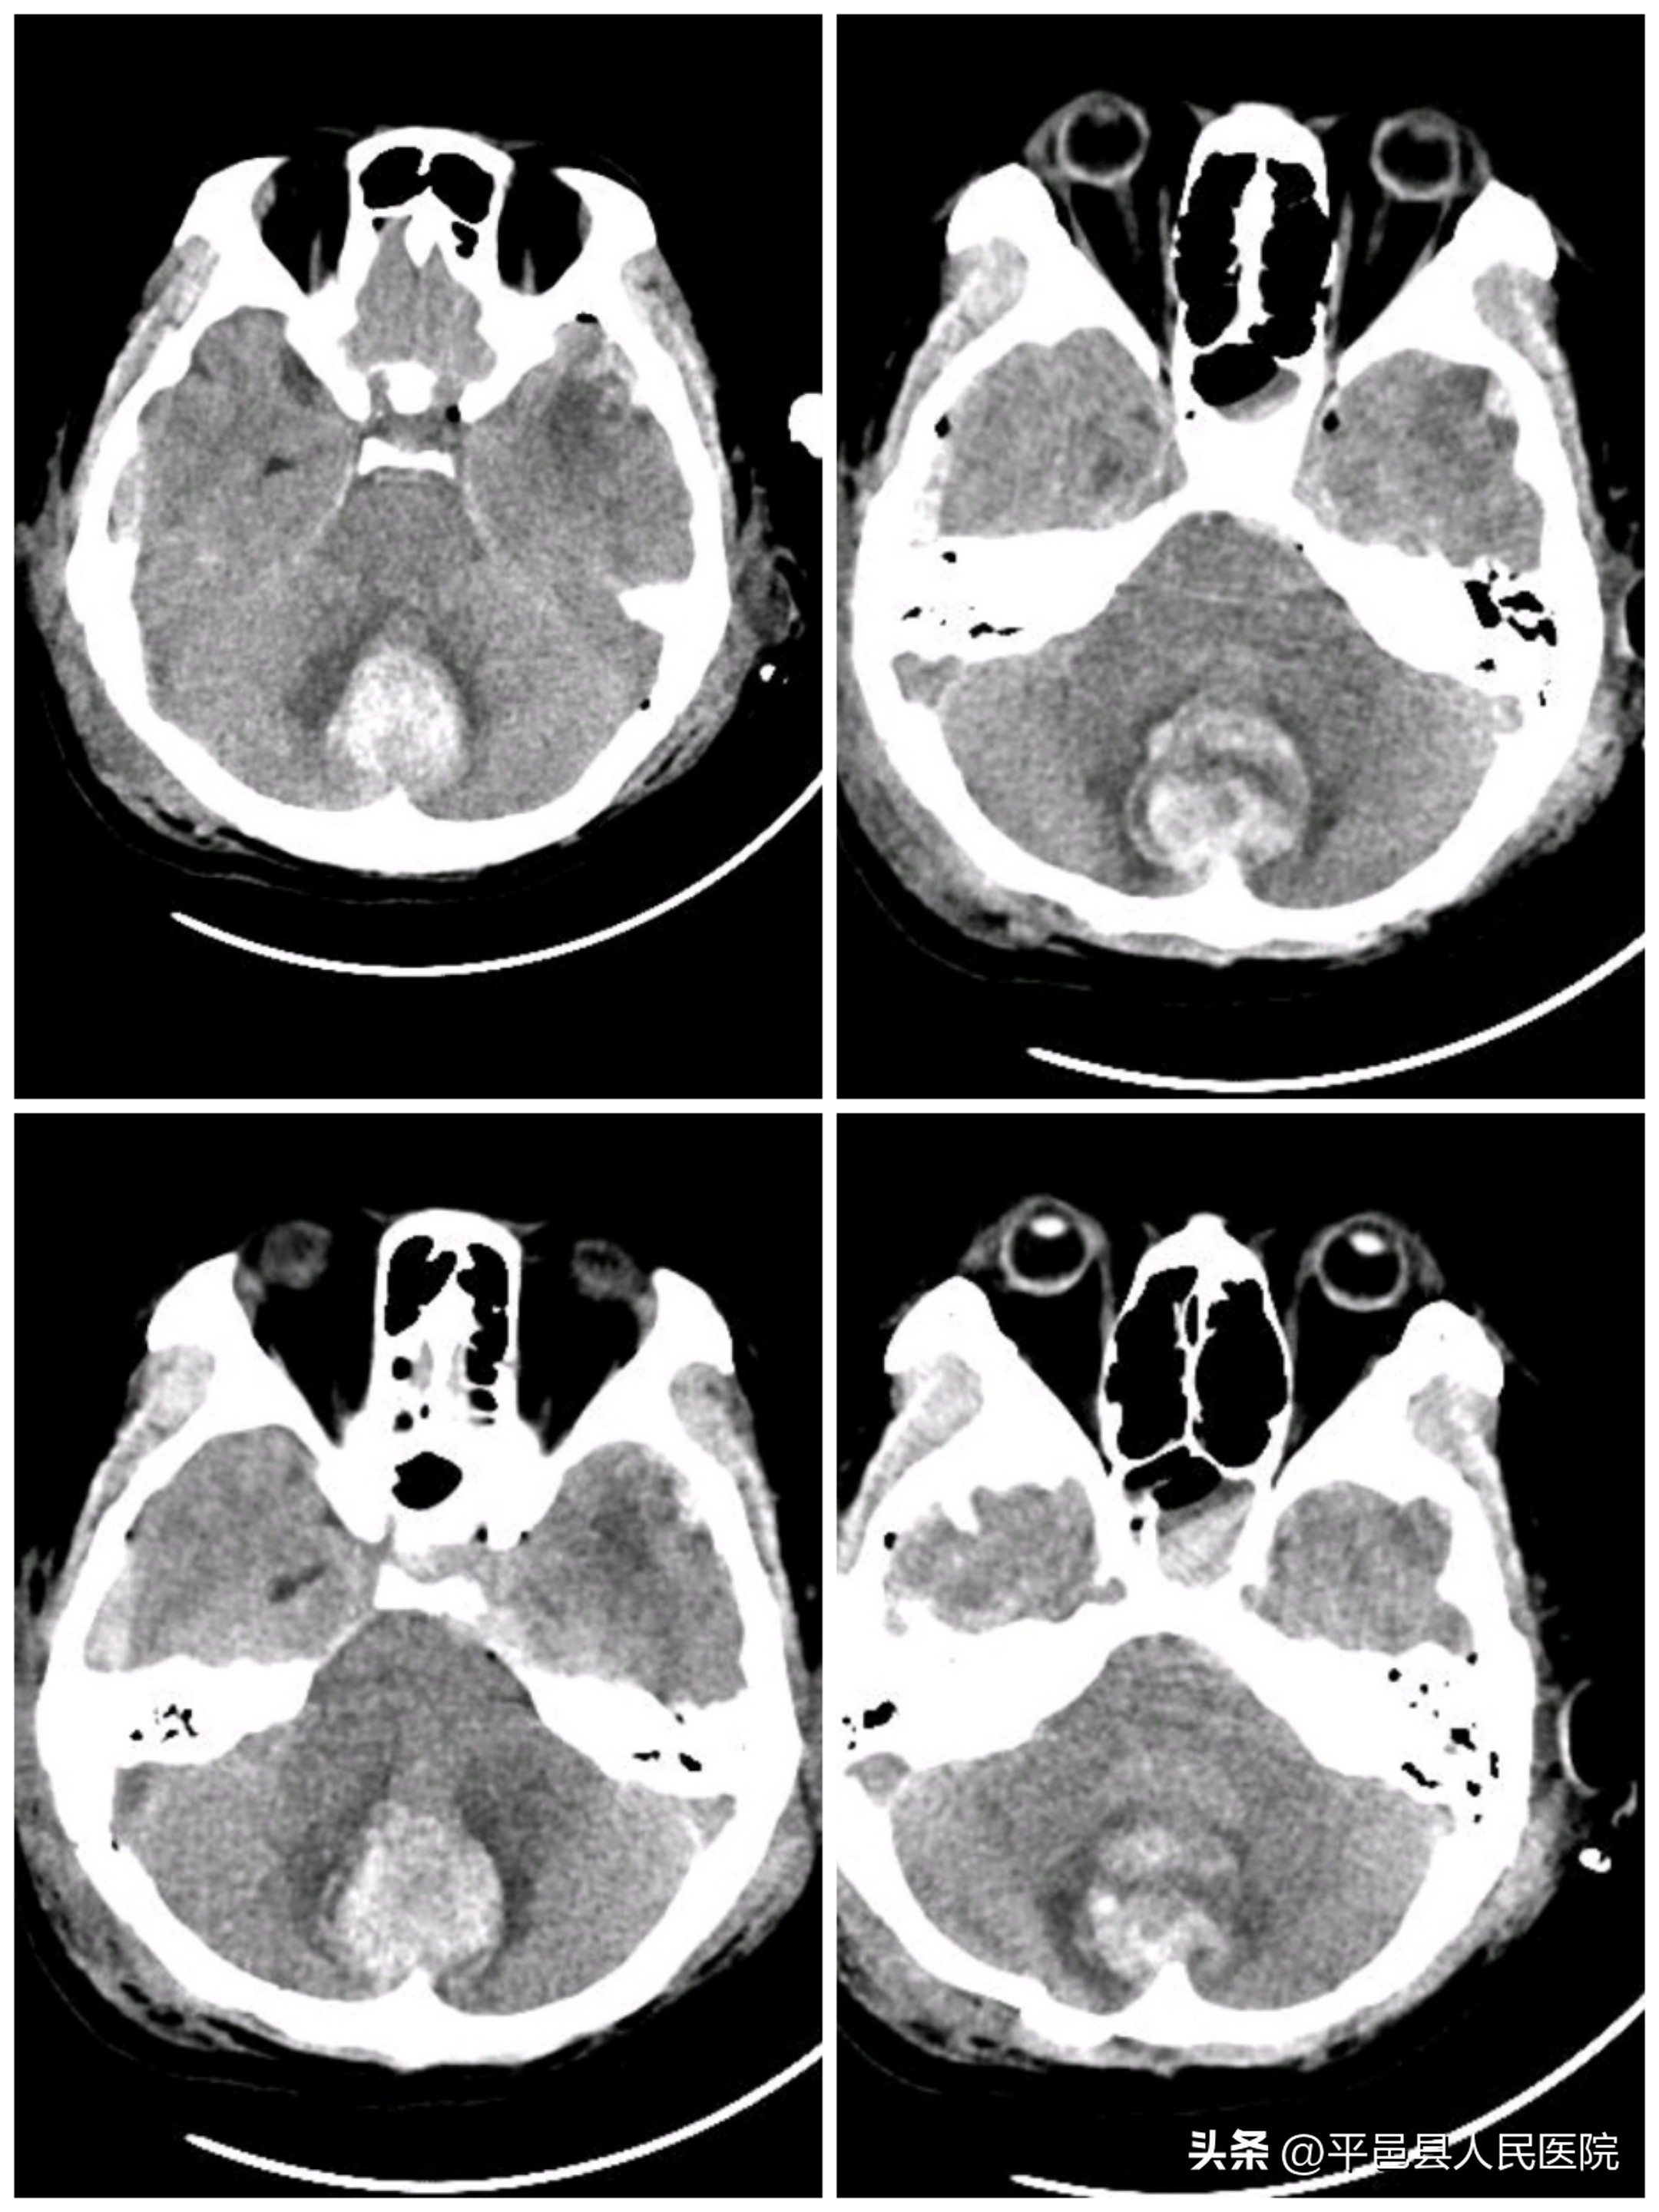

小脑挫裂伤并脑内血肿压迫脑干

枕骨粉碎性骨折累及枕骨大孔

随后多发性小脑挫裂伤、小脑血肿、枕骨凹陷、粉碎性骨折由神经外科二病区紧急行小脑血肿清除、枕骨粉碎骨折清除减压手术,同时给予输血、补液纠正休克,手术顺利完成。术后转入神经外科二病区继续治疗额颞叶多发大脑挫裂伤、硬脑膜下血肿、硬膜外血肿。